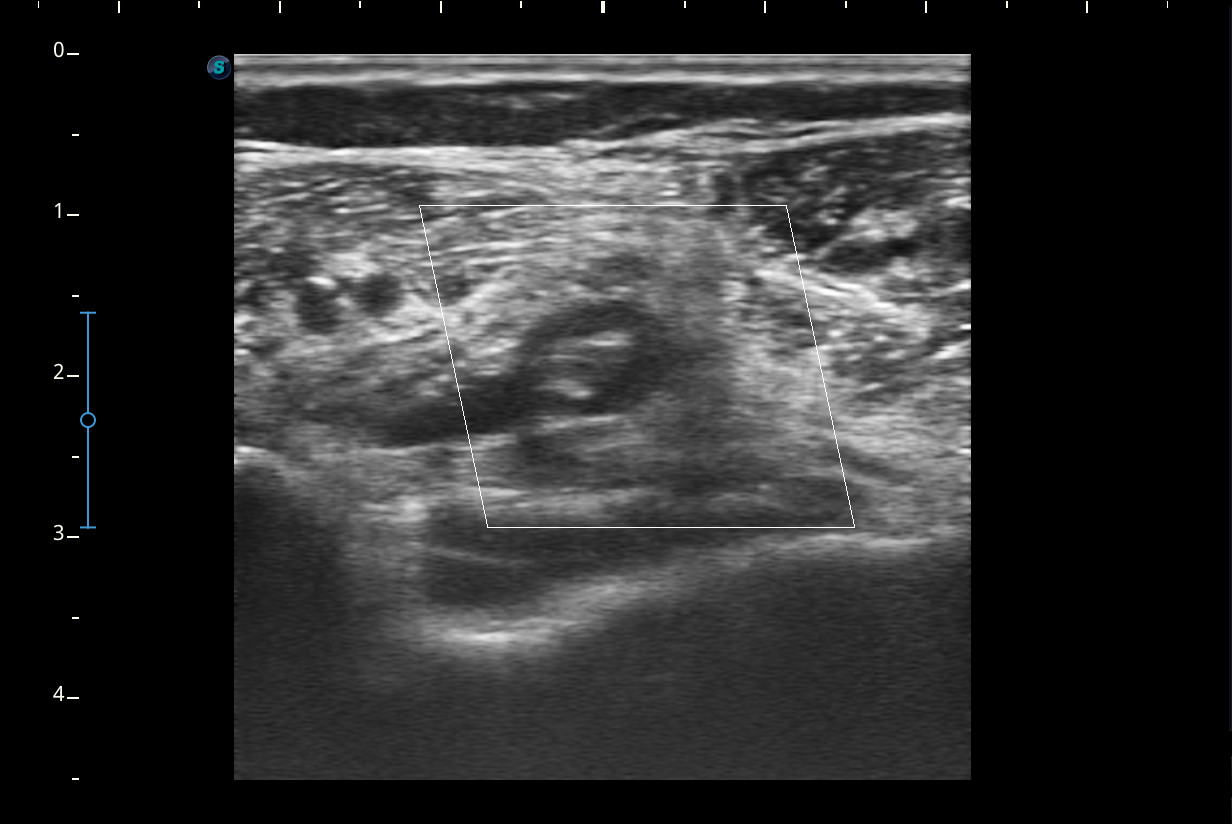

Mujer de 44 años, que presenta desde hace 2-3 semanas dolor e impotencia funcional en la pierna derecha con aumento de volumen y eritema de pantorrilla ipsilateral que en un inicio se trató como rotura fibrilar para la que se pauta reposo y tratamiento analgésico oral. Ha mejorado muy levemente pero persiste dolor en el hueco popliteo e impotencia funcional.Descripción de los hallazgos ecográficos y las imágenes más relevantes para la resolución del caso

A nivel del hueco poplíteo se visualiza presencia de trombosis de la vena poplítea, no así en localizaciones proximales.Otras pruebas complementarias realizadas (si existen)